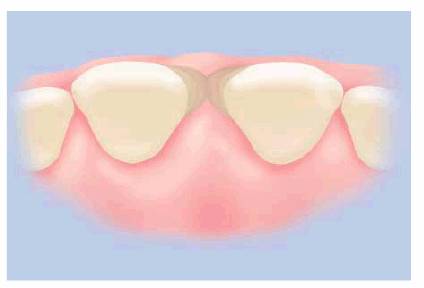

The most practical restorative treatment to eliminate a

small diastema between sound teeth is by direct bonding with composite resin (Figures 23-12A and B, 23-12C, 23-12D, 23-12E, 23-12F, 23-12G and H). Direct composite resin bonding is fast (one

appointment) and reversible because mechanical tooth preparation is often

unnecessary.12 If an improved material or technique becomes

available, it is relatively easy to remove the existing bonded composite and

use the new method. Economics is an additional advantage for the use of direct

composite resin bonding as this technique is approximately one-third to one

half the cost of porcelain laminates or crowns. The ability to save time,

money, and tooth structure makes composite resin a popular choice with many

dentists and patients.

Figure 23-12A and B: The most practical method for closing a simple diastema is with composite resin bonding.

Figure 23-12C: Many times, it will be necessary to adjust the occlusion on the opposing arch to lessen the stress on the bonded incisors.

Figure 23-12D: This drawing illustrates that the composite resin will be bonded to labial, mesial, and lingual surfaces.

Figure 23-12E: It is important to measure the size of the space to be closed and bond each tooth separately using one half of the space for each tooth.

Figure 23-12F: The space is now closed. Note how invisible a self-contoured and polished margin can be.

Figure 23-12G and H: The before and after comparison seems to confirm what this patient said: that even a small diastema can be distracting while observing the entire smile.